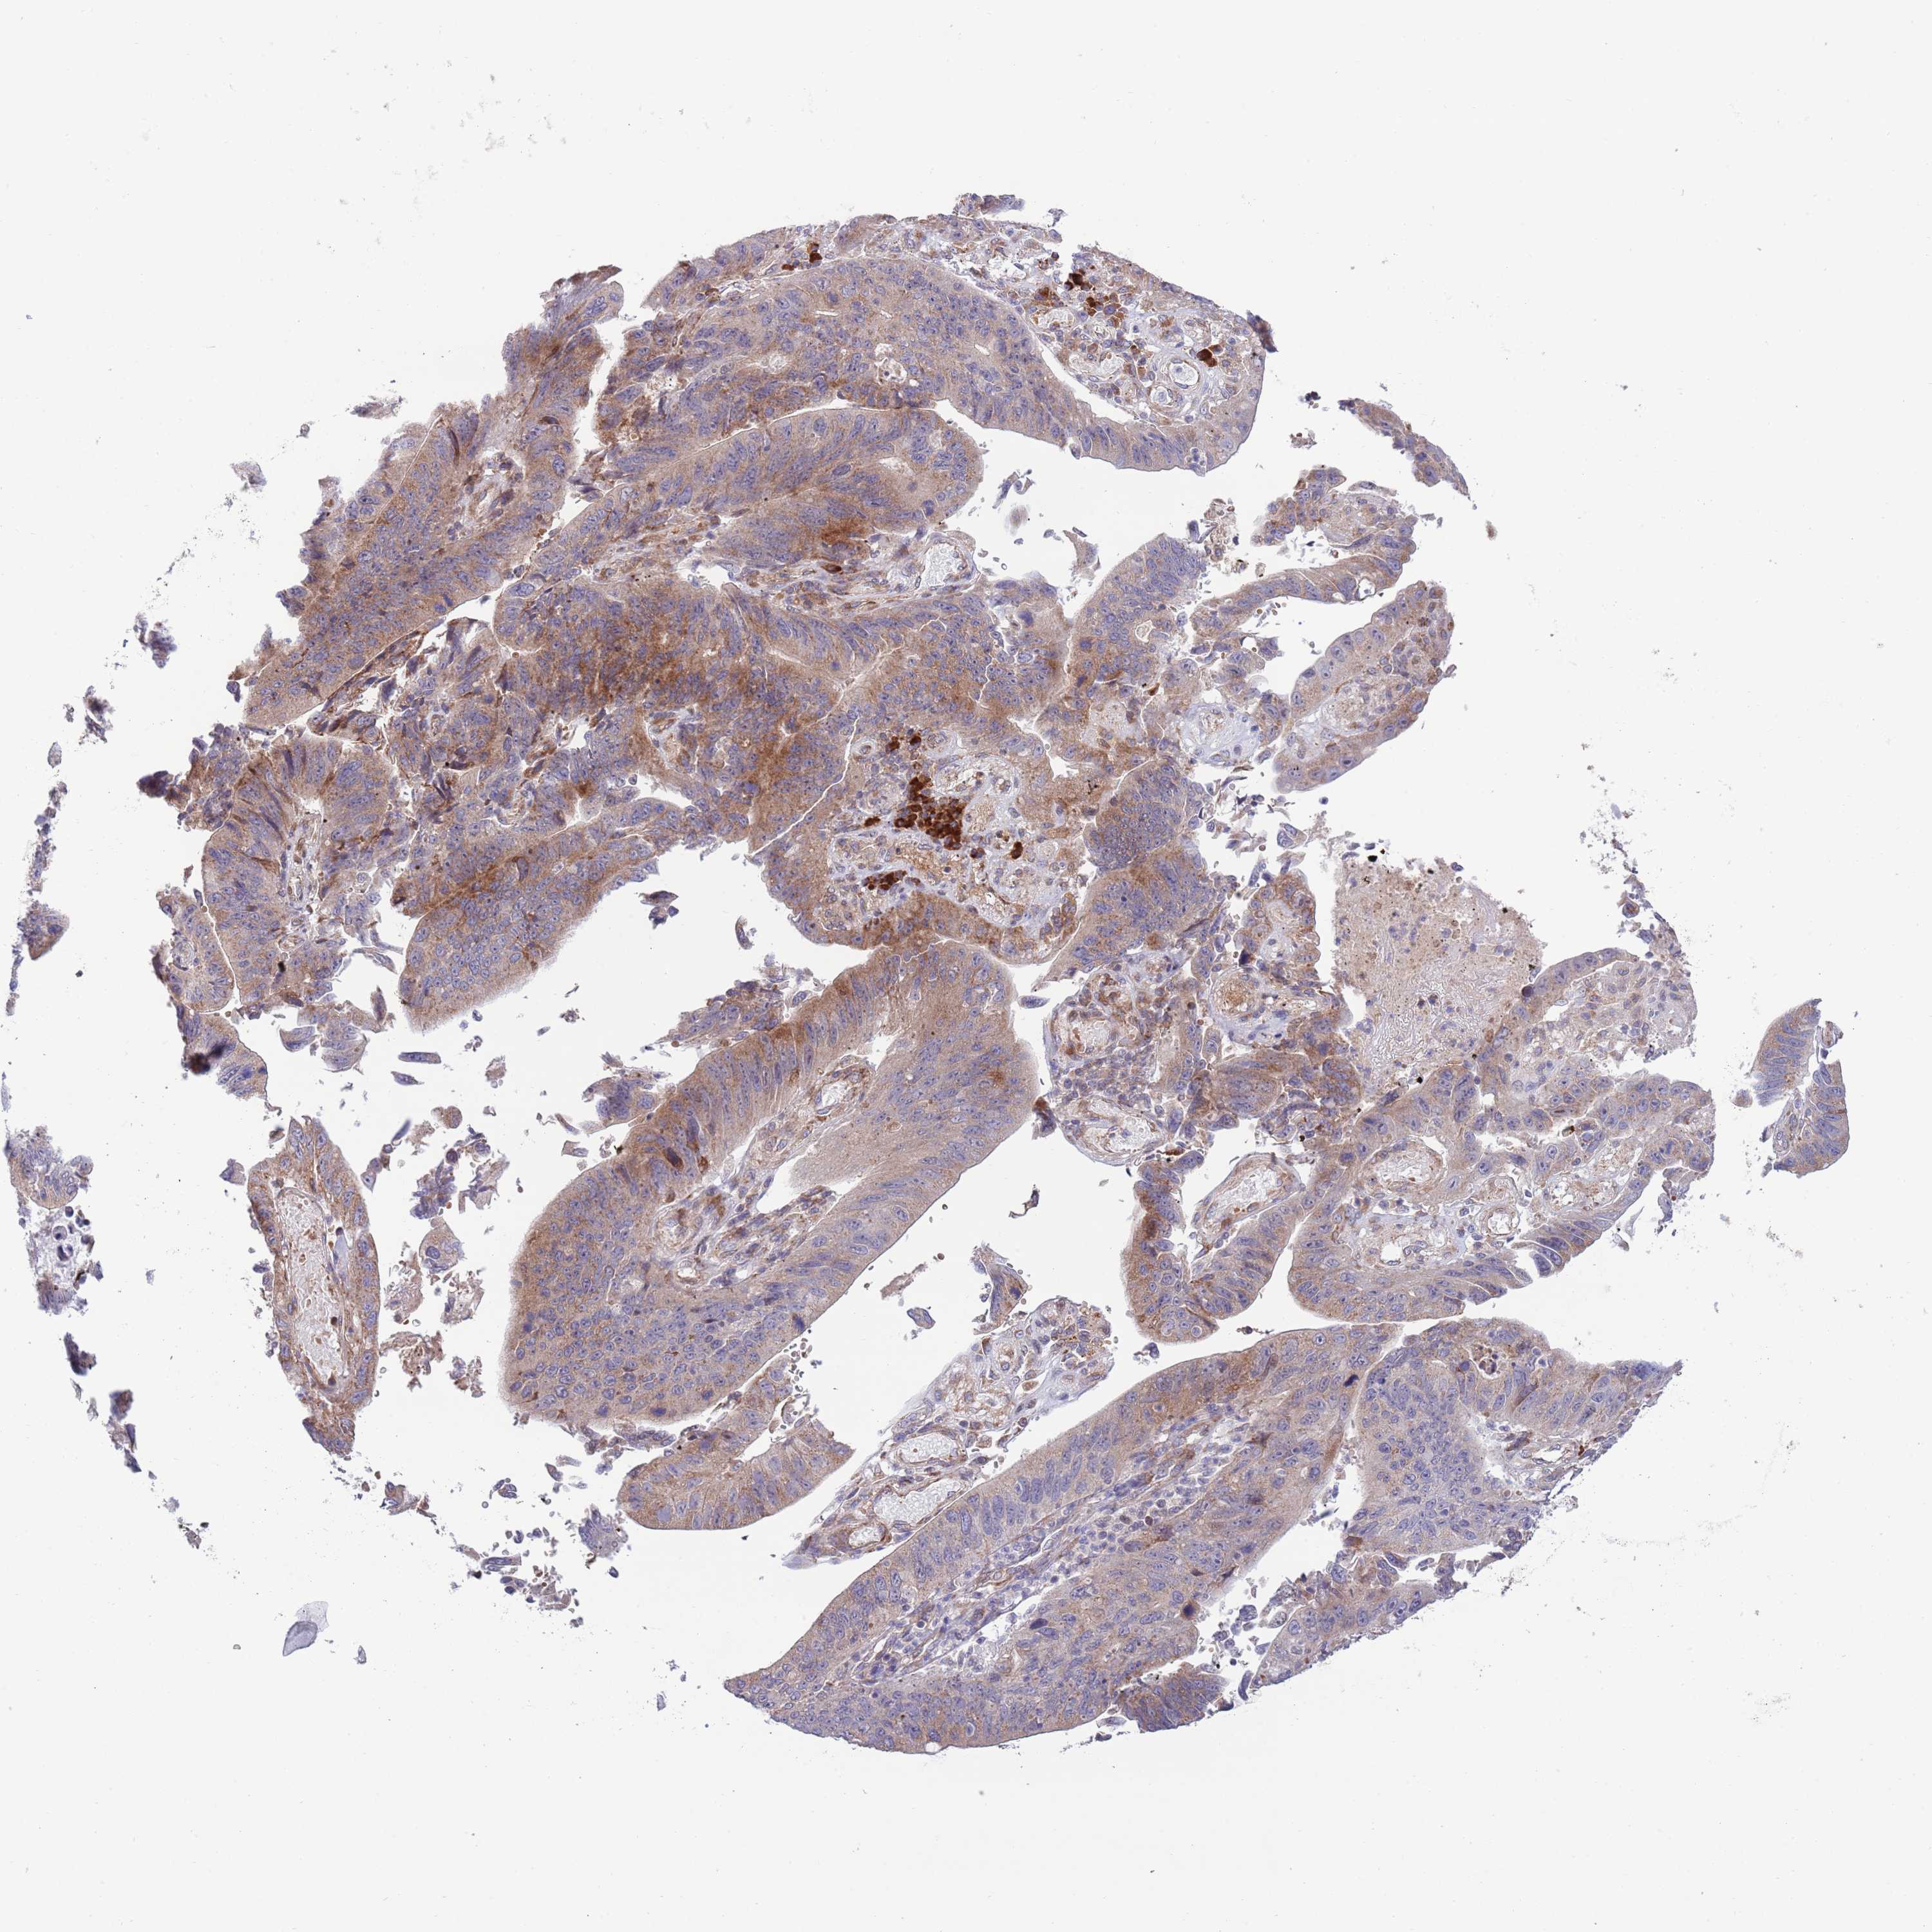

STOMACH CANCER - Protein expressioni

A mouse-over function shows sample information and annotation data. Click on an image to view it in a full screen mode. Samples can be filtered based on level of antibody staining by selecting one or several of the following categories: high, medium, low and not detected. The assay and annotation is described here.

Note that samples used for immunohistochemistry by the Human Protein Atlas do not correspond to samples in the TCGA dataset.

Antibody stainingi

Antibody staining in the annotated cell types in the current human tissue is reported as not detected, low, medium, or high, based on conventional immunohistochemistry profiling in selected tissues. This score is based on the combination of the staining intensity and fraction of stained cells.

Each image is clickable and will lead to virtual microscopy that enables deeper exploration of all samples and also displays staining intensity scores, fraction scores and subcellular localization as well as patient and tissue information for each sample.

Antibody HPA049472

Staining

High

Medium

Low

Not detected

Intensity

Strong

Moderate

Weak

Negative

Quantity

>75%

75%-25%

<25%

None

Location

Nuclear

Cytoplasmic/membranous

Cytoplasmic/membranous,nuclear

Adenocarcinoma, NOS